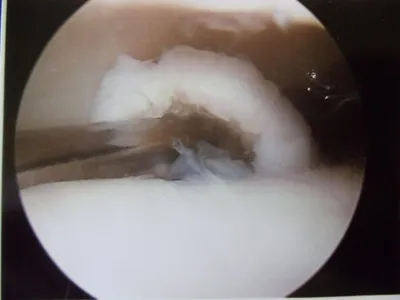

The following pictures are debridement of damaged cartilage that is abnormal in appearance and/or loose. This is removed completely to expose the subchondral (underneath cartilage) bone plate.

Drill holes are then placed through the bone plate to allow bleeding in the area, which will aide in healing of the cartilage surface with fibrocartilage, which is a kind of scarring of cartilage.

Debridement and Curettage of loose and damaged cartilage

Microfracture/subchondral drilling of bone to stimulate fibrocartilage growth.